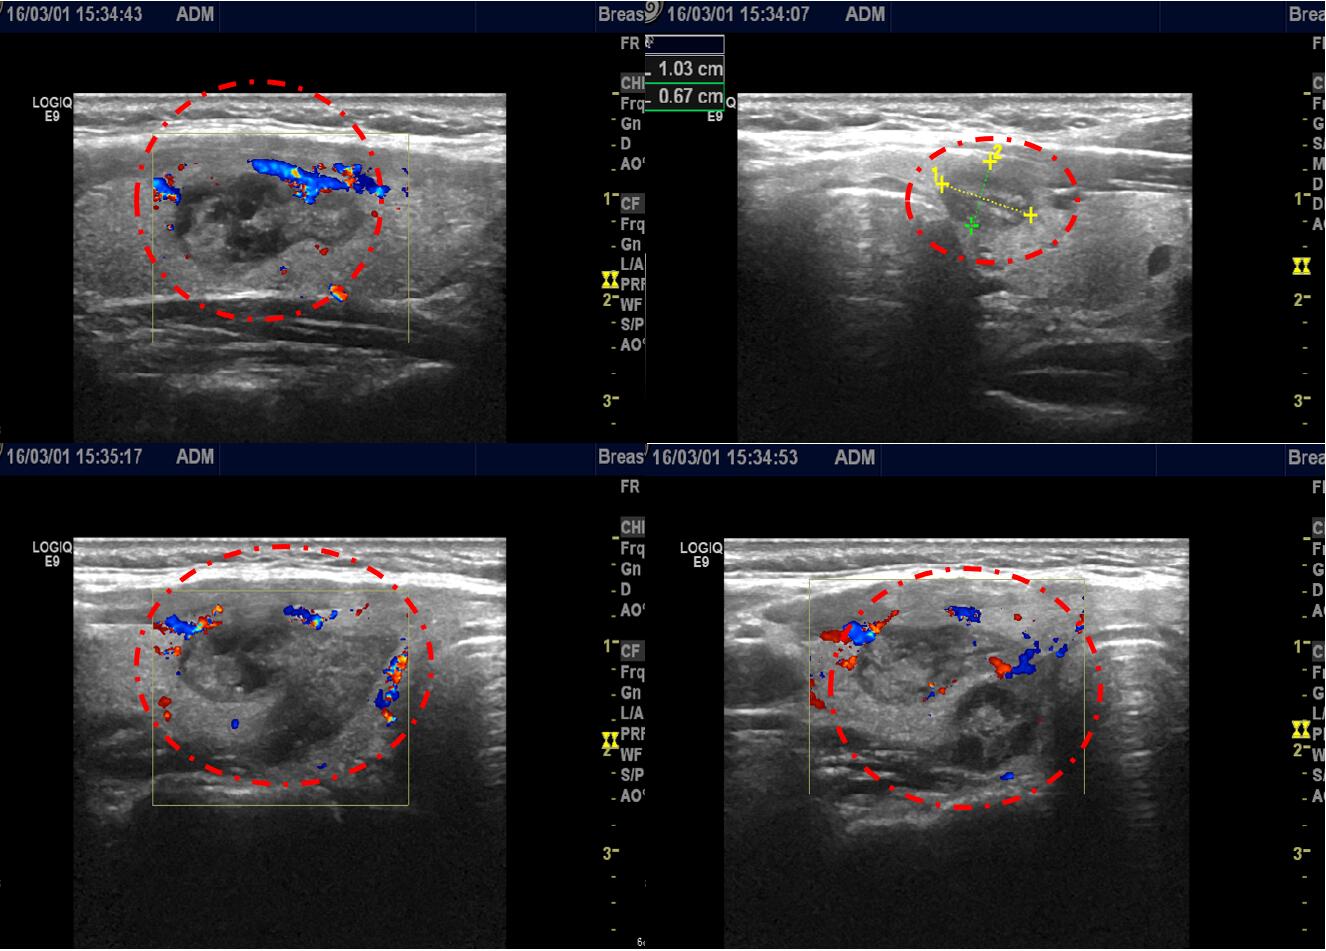

介入科医生先给予李女士在超声引导下行甲状腺结节细针穿刺活检化验未发现恶性细胞,随后给予李女士在超声引导下行甲状腺双侧叶多发结节消融治疗,微创介入消融治疗后恢复良好,第2天出院,颈部小针眼已愈合,没有疤痕(如下图)。

李女士微创介入消融治疗后2个多月复查甲状腺功能正常,超声显示甲状腺多发结节均完全消融,消融边界清晰(如下图)。